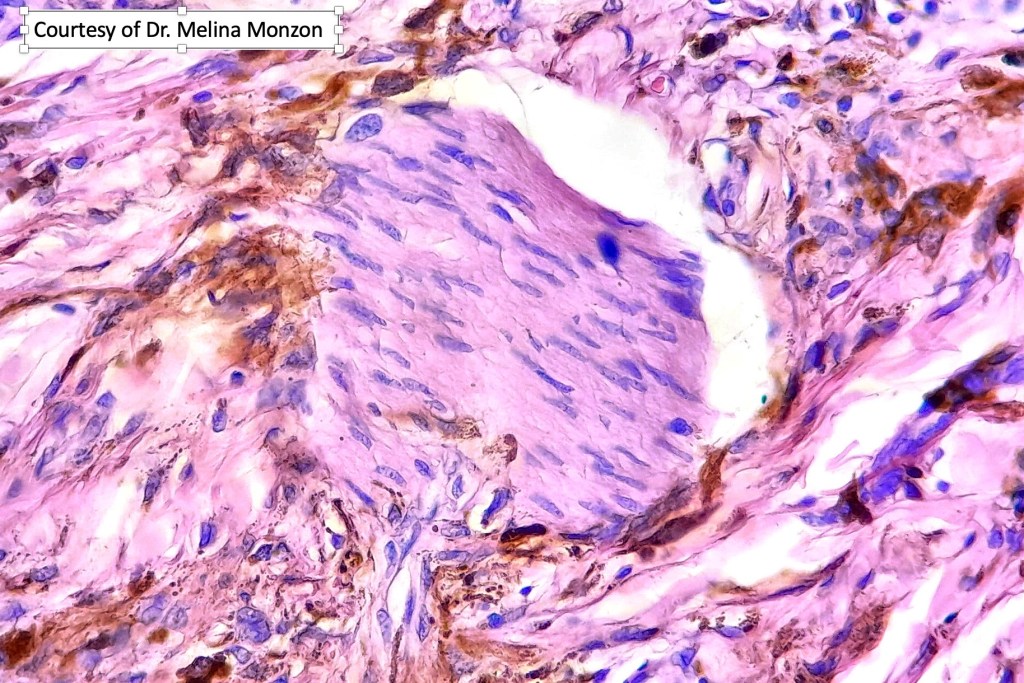

Histologically the features are very subtle and may require a Masson Fontanna stain or immunohistochemistry for diagnosis. Small numbers of dendritic melanocytes are present in the deep dermis siad to be orientated parallel to the epidermis.

Histologically, both lesions are characterized by the presence of denritic melanocytes in the upper & mid dermis. The overlying epidermis is often hperpigmented and increased numbers of melanocytes are sometimes evident.

Histologically, it is characterized by a dense population of spindled, dendritic melnanocytes & melanophages with variable fibrosis. It may sometimes represent a component of a combined nevus. Mitotic activity is not usually present and pleomorphism is absent (see atypical blue nevus below). Involvement of the arrector pili muscle is not uncommon.